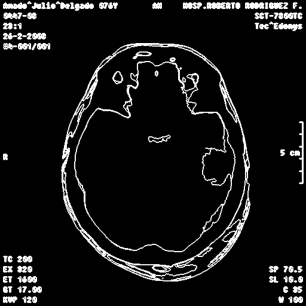

An example of an applications of our proposed strategy to a medical image is shown in Figure 7. In this case, we used different values of and in the . This is a preliminary result. A deeper paper about these results will be published.